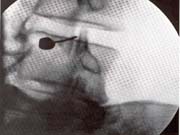

<ÈİüÀý°³»

ÁÖ»ç¿ä¹ý>